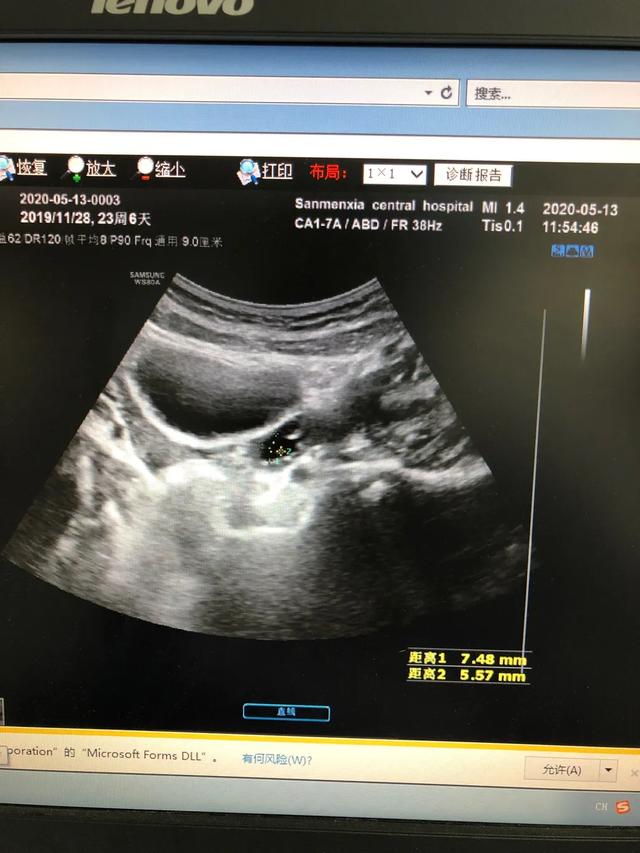

下图是一例患儿性早熟的B超结果、胸片结果及血清学化验结果。

从检查结果来看,B超显示子宫卵巢有囊性回声;胸片显示乳腺发育;而血清学指标,促黄体生成素的峰值是13.09,促卵泡的峰值是20.91,LH/FSH=62.60%。